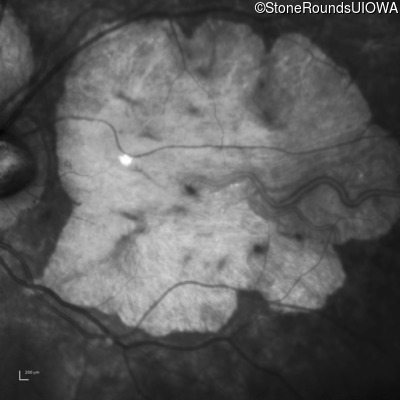

Age at visit: 43 years

OD OS